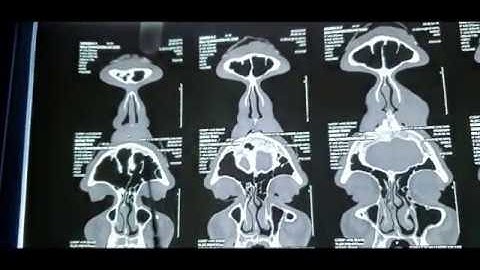

How to read a CT PNS | All points Explained in detail